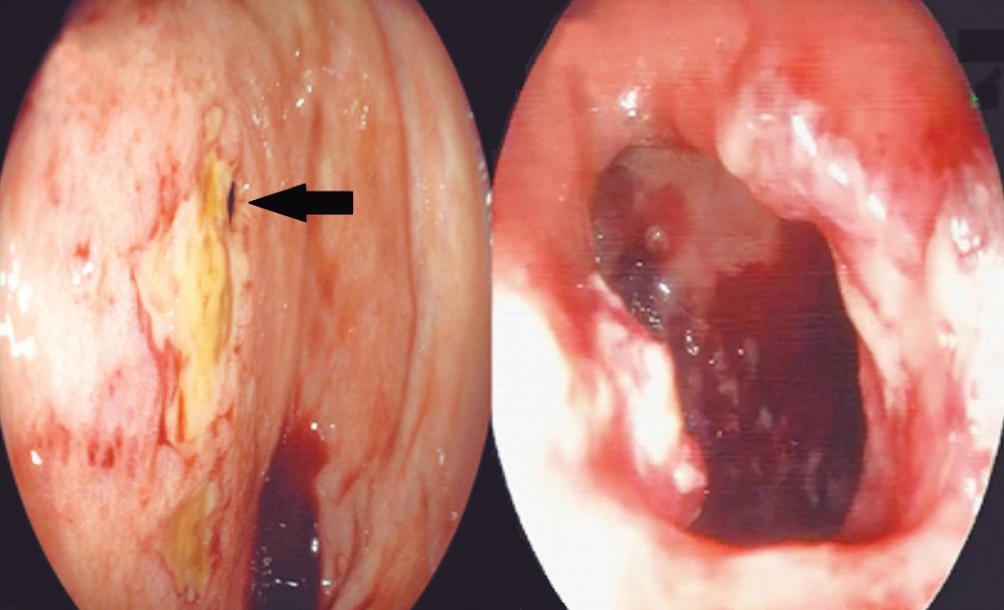

Necrosectomía endoscópica transmural a través de fístula pancreático gástrica espontánea secundaria a necrosis encapsulada infectada

Juan Ramirez García, César Vargas-Alayza, Natali Ravelo

6 ACTA GASTROENTEROL LATINOAM - MARZO 2023:VOL 53:Nº1 u INDEX SOLUTION OF THE CASE Complications of Congenital Pathologies in Adulthood Ezequiel Balaban, María Laura Moreno, Mauricio Paternó, Florencia Costa, Daniela Milito, María Eugenia Oregui 94 Transmural Endoscopic Necrosectomy through a Spontaneous Gastric-Pancreatic Fistula Secondary to Infected Encapsulated Necrosis Juan Ramirez García, César Vargas-Alayza, Natali Ravelo 90 CASE REPORTS Intracholecystic Papillary Neoplasm: Rare Pathology of the Gallbladder. A Diagnostic Challenge Patricia López Penza, Mauro Mallarino, Alejandro Etcheverry, María Oreggia, Gustavo Burghi 84 Use of Autologous Platelet-Rich Plasma in the Treatment of Chronic Anal Fissure: A Case Series Neith Ortega Pérez 76 ORIGINAL ARTICLES

Acta Gastroenterol Latinoam 2023;53(1):7-10